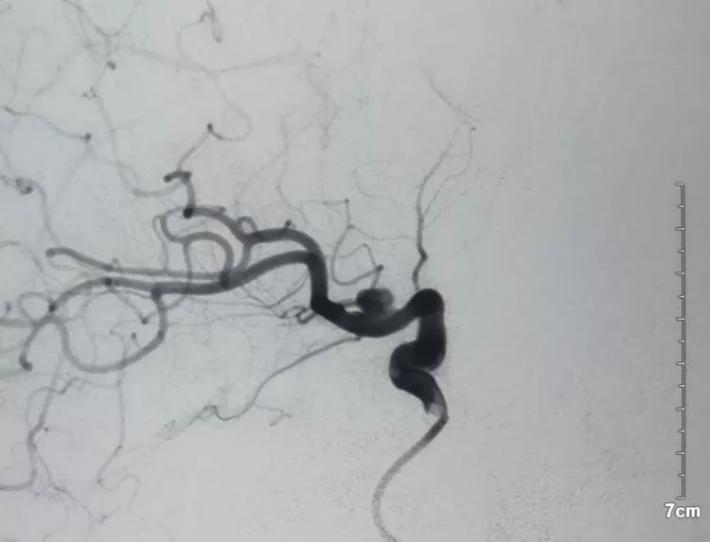

3D重建见BBA夹闭完全,脉前A(黄箭头)保留完好,局部颈内动脉通畅,桥血管通畅无吻合口狭窄(白箭头)!

超选ECA造影,STA→MCA桥通畅,MCA皮层支显影充分!

3D动态见BBA不显影,局部ICA管腔略窄,脉前A/STA→MCA吻合口通畅,手术达到预期效果,STA另支血管搭桥不需要了,关颅结束手术! 结论 术后CT未见MCA区域新发缺血,病人康复有望!